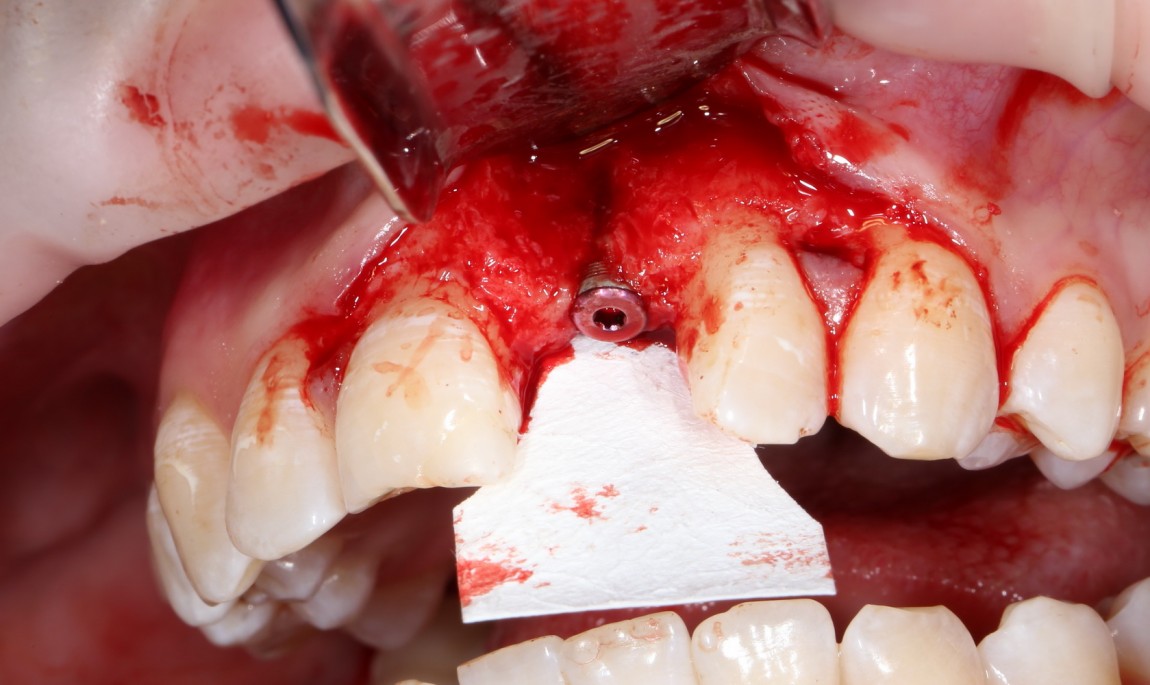

Итого, наиболее оптимальным в данной ситуации оказалась направленная тканевая регенерация с использованием барьерных мембран. В качестве барьерной мембраны у нас будет Geistlich BioGide. Ее очень легко адаптировать и позиционировать:

А в качестве трансплантата — аутокостная стружка, которую я насобирал заранее из области угла нижней челюсти:

Начну с того, что BioGide — это лучшее, что есть сейчас на рынке, а остальные мембраны ей завидуют. Как и в случае с макродизайном имплантов, именно физические свойства определяют как удобство использования, так и возможность достижения нужного результата. Прочность, эластичность, легкая адаптация и адгезия делают ненужными использование фиксирующих пинов. Мы просто закрываем мембраной графт — и все, можно накладывать швы:

В другом ракурсе видно, какой объем тканей мы восстанавливаем:

и теперь швы. Наглухо (Фактор II):

Вот так мы сочетаем имплантацию с остеопластикой. И, если мы сделали все по правилам и без противоречий здравому смыслу, то через 3 месяца мы должны получить неплохой результат.